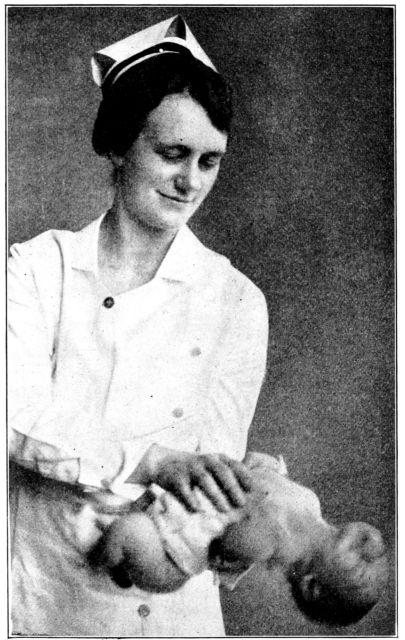

| 167. | Proper method of carrying baby | 487 |